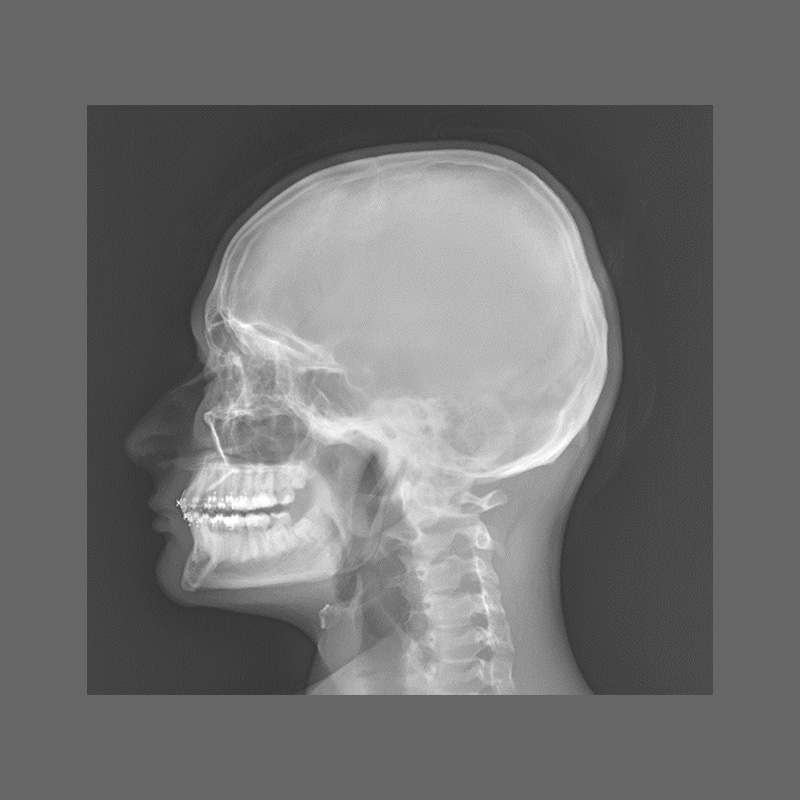

КЛІНІЧНА ГАЛЕРЕЯ GENÈVE 40M: